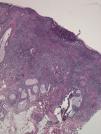

HistopathologyHistologic examination revealed a cutaneous ulcer with necrotizing vasculitis and a mixed neutrophilic and eosinophilic infiltrate in perivascular and interstitial areas (Figs. 2 and 3). Cultures, Gram stain, and direct immunofluorescence were negative.